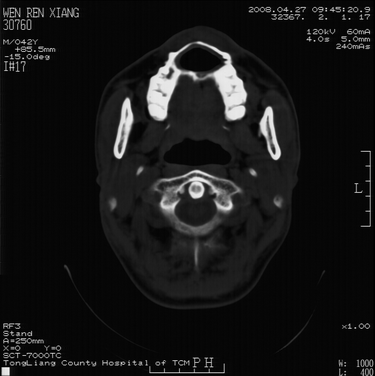

以下是引用随光逐影在2008-4-27 10:26:00的发言:[br]考虑为:上颌骨(中线区)含牙囊肿并向鼻腔穿破。

以下是引用前行在2008-4-27 11:30:00的发言:[br]含牙囊肿可能性大

以下是引用余辉在2008-4-27 16:43:00的发言:[br]考虑上颌骨正中囊肿,伴不全上颌骨正中裂,囊肿与鼻前庭有瘘道,所以表现为腔内炎性粘膜增厚而无囊液